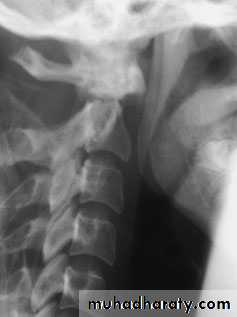

Cervical Spine X-RayLateral radiograph

A/P radiographThoracic Anatomy

The patient will usually give a history of a fall from a height, a diving accident or a vehicle accident in which the neck is forcibly moved. In a patient unconscious from a head injury, a fractured cervical spine should be assumed (and acted upon) until proved otherwise.An abnormal position of the neck is suggestive, and careful palpation may elicit tenderness.

Plain x-rays show either a crushed vertebral body(burst fracture) or a flexion deformity with a triangular fragment separated from the antero-inferior edge of the fractured vertebra (the innocent-looking ‘teardrop’).